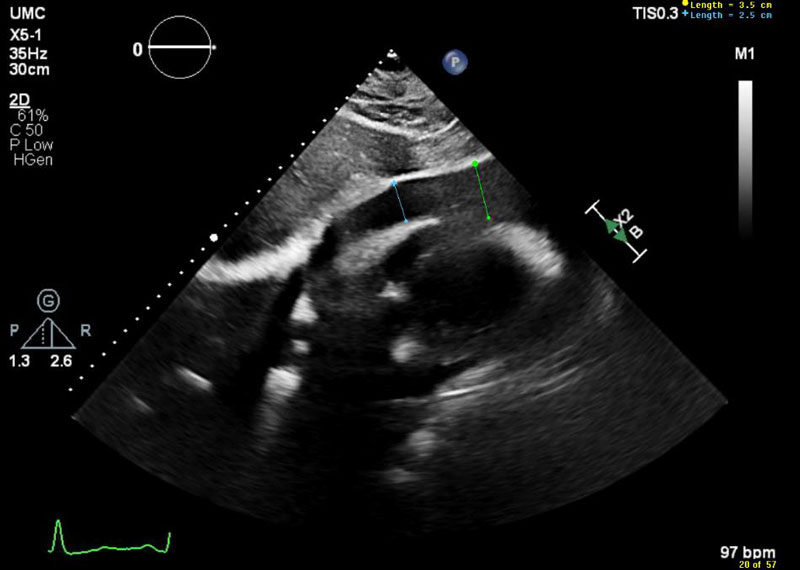

A 57-year-old female patient with medical history of well-controlled hypothyroidism and newly diagnosed hypertension reported a two-month history of progressively worsening shortness of breath and a dry cough, which became more pronounced with exertion and when lying flat. She denied any recent illness, or travel. Her primary care physician referred her for an outpatient echocardiogram, which revealed a large pericardial effusion with echocardiographic signs of tamponade (Figure 1, Videos 1, 2, 3). This critical finding prompted immediate notification of our cardiology team.

Figure 1

Figure 1 Subcostal view showing large pericardial effusion measuring up to 3.5 cm in diastole.